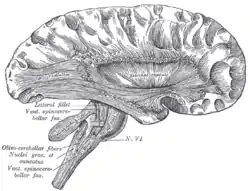

Deep dissection of cortex and brain-stem. (External capsule visible at center.)

External capsule

The external capsule is a series of white matter fiber tracts in the brain. These fibers run between the most lateral (toward the side of the head) segment of the lentiform nucleus (more specifically the putamen) and the claustrum.